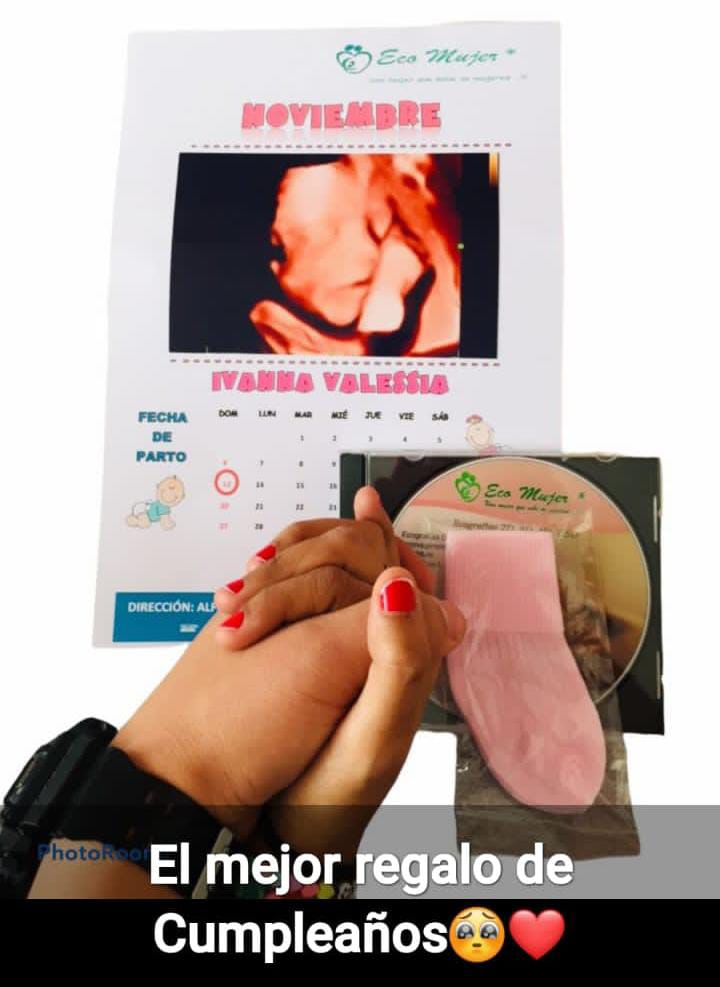

Obsequios Exclusivos

Detalles únicos hechos a mano con amor, en colaboración con Kibela.

Detalles que Enamoran

- Piezas de arte para tu bienestar.

- Jabones naturales y accesorios tejidos.

- Apoyo a Kibela (emprendimiento local).

¡Tu experiencia será inolvidable!